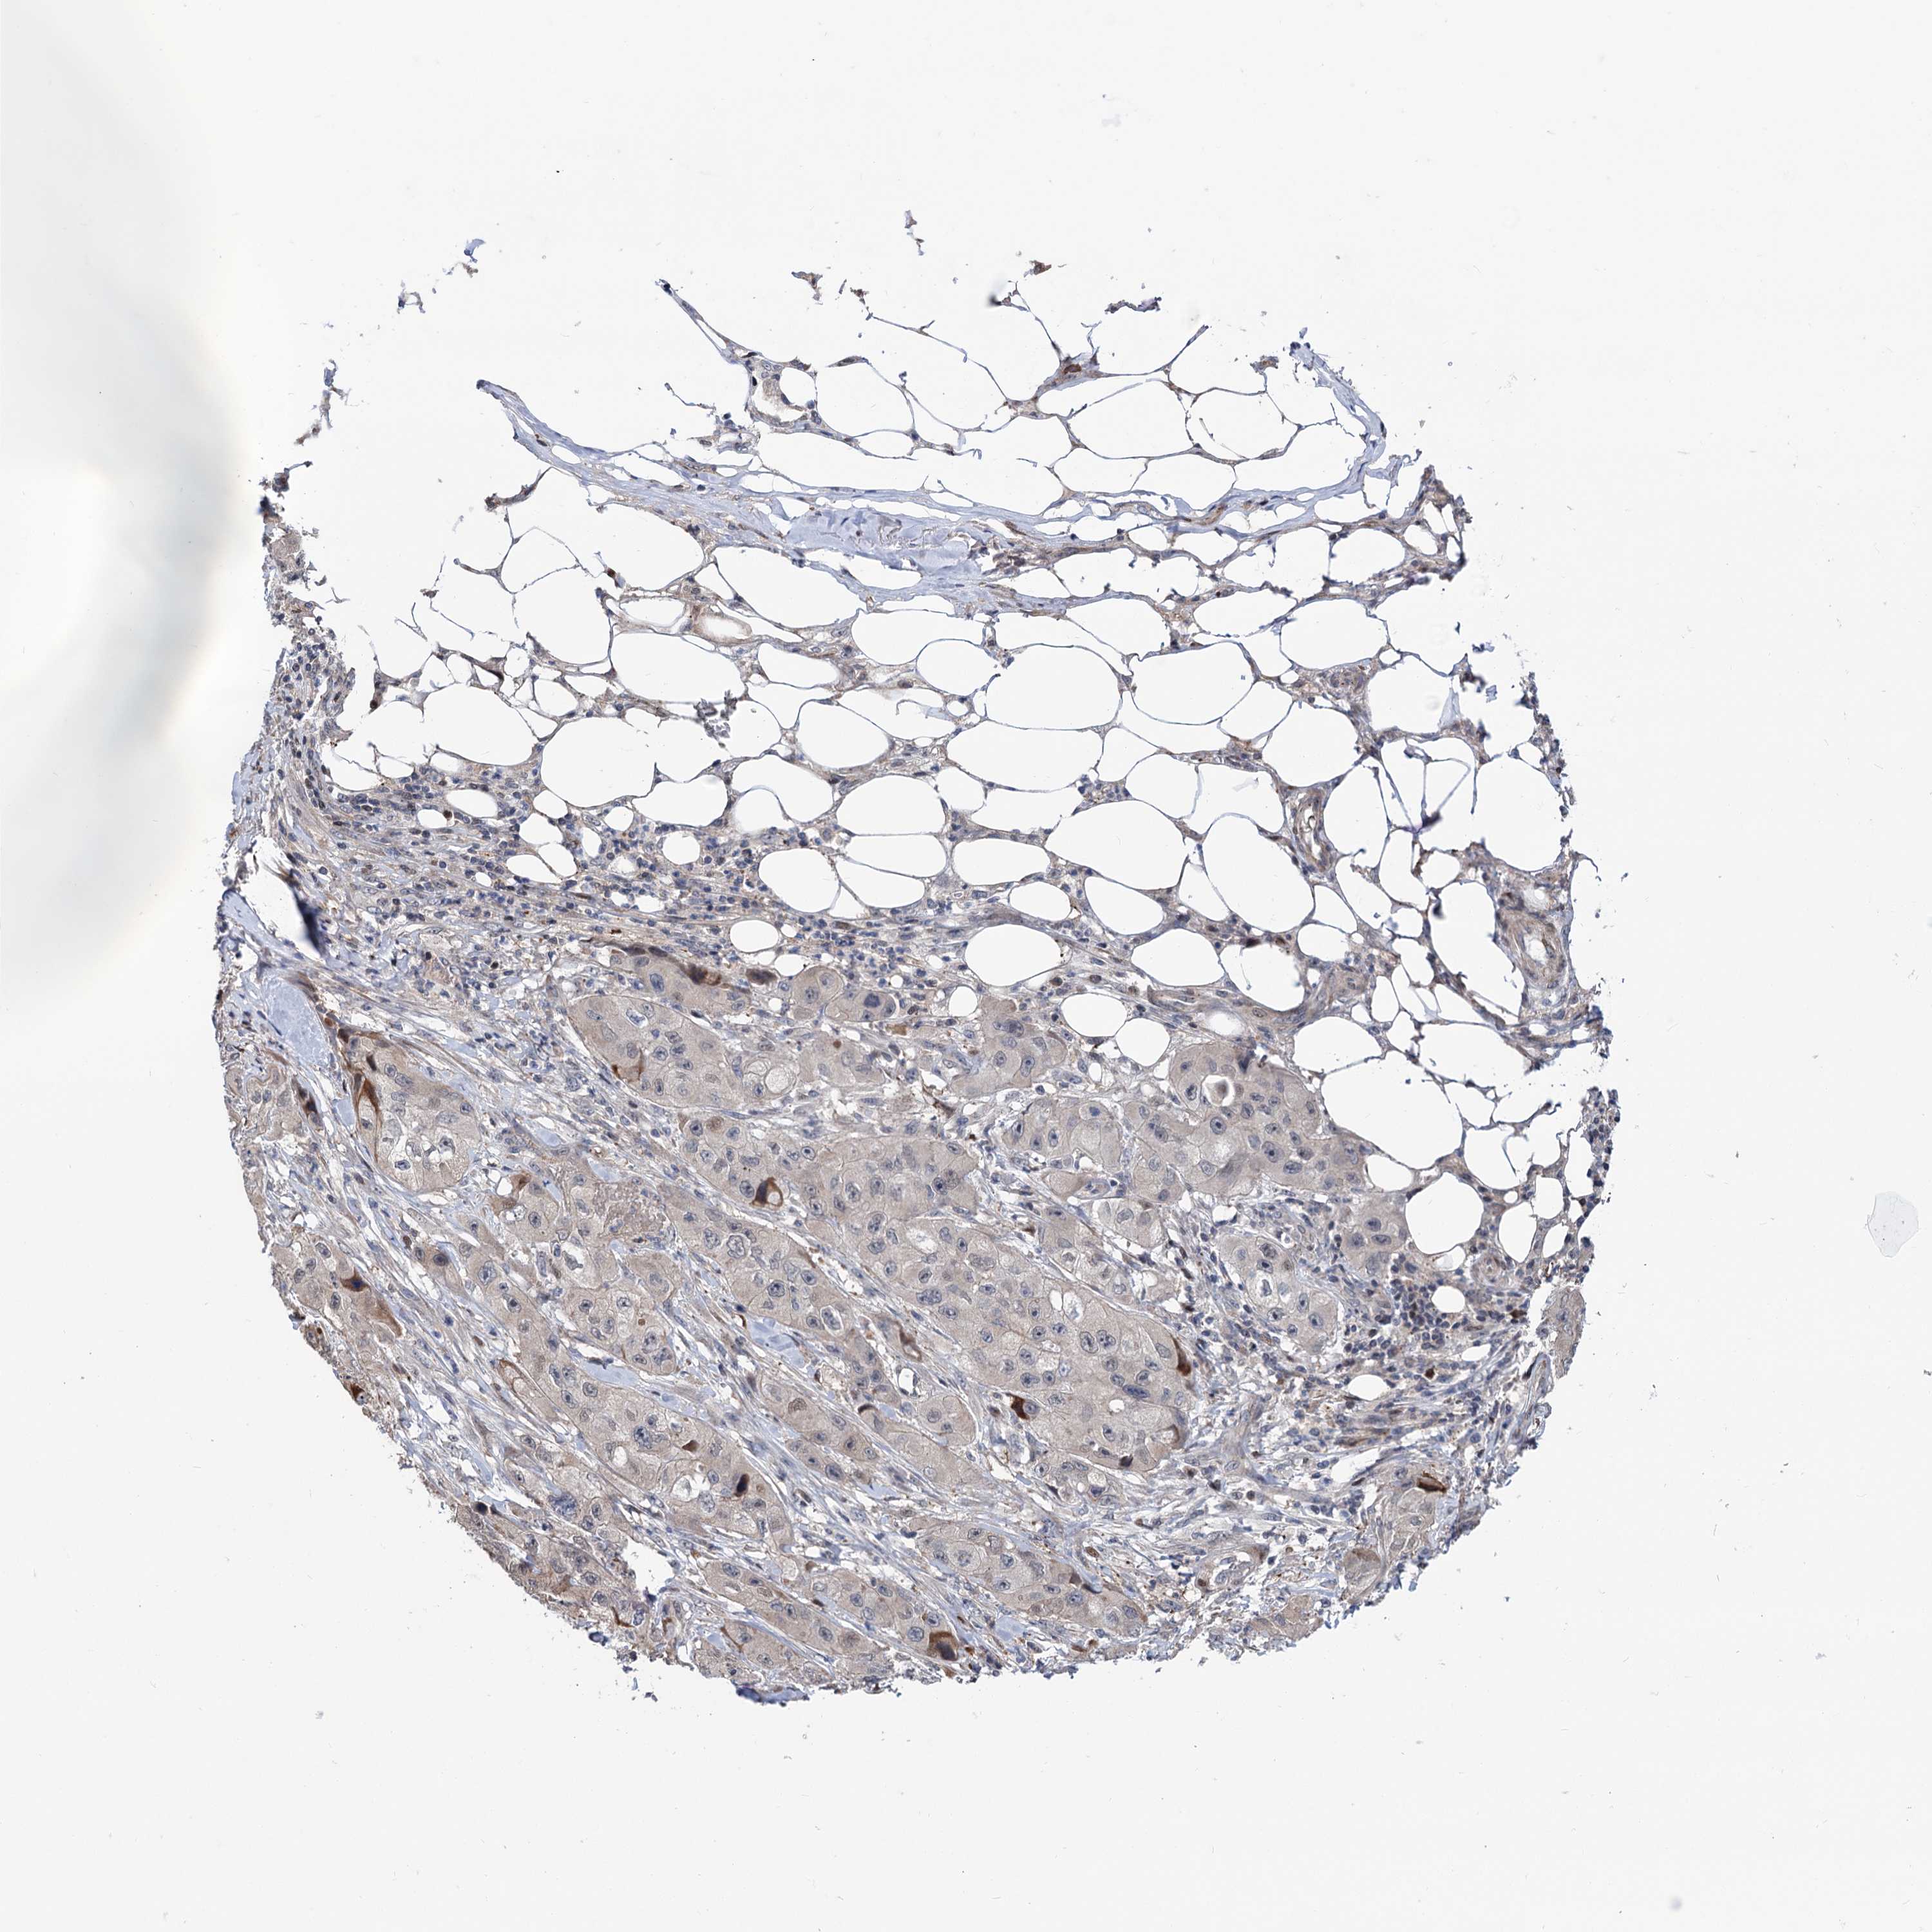

SKIN CANCER - Protein expressioni

A mouse-over function shows sample information and annotation data. Click on an image to view it in a full screen mode. Samples can be filtered based on level of antibody staining by selecting one or several of the following categories: high, medium, low and not detected. The assay and annotation is described here.

Antibody stainingi

Antibody staining in the annotated cell types in the current human tissue is reported as not detected, low, medium, or high, based on conventional immunohistochemistry profiling in selected tissues. This score is based on the combination of the staining intensity and fraction of stained cells.

Each image is clickable and will lead to virtual microscopy that enables deeper exploration of all samples and also displays staining intensity scores, fraction scores and subcellular localization as well as patient and tissue information for each sample.

Antibody HPA046727

Squamous cell carcinoma, metastatic, NOS